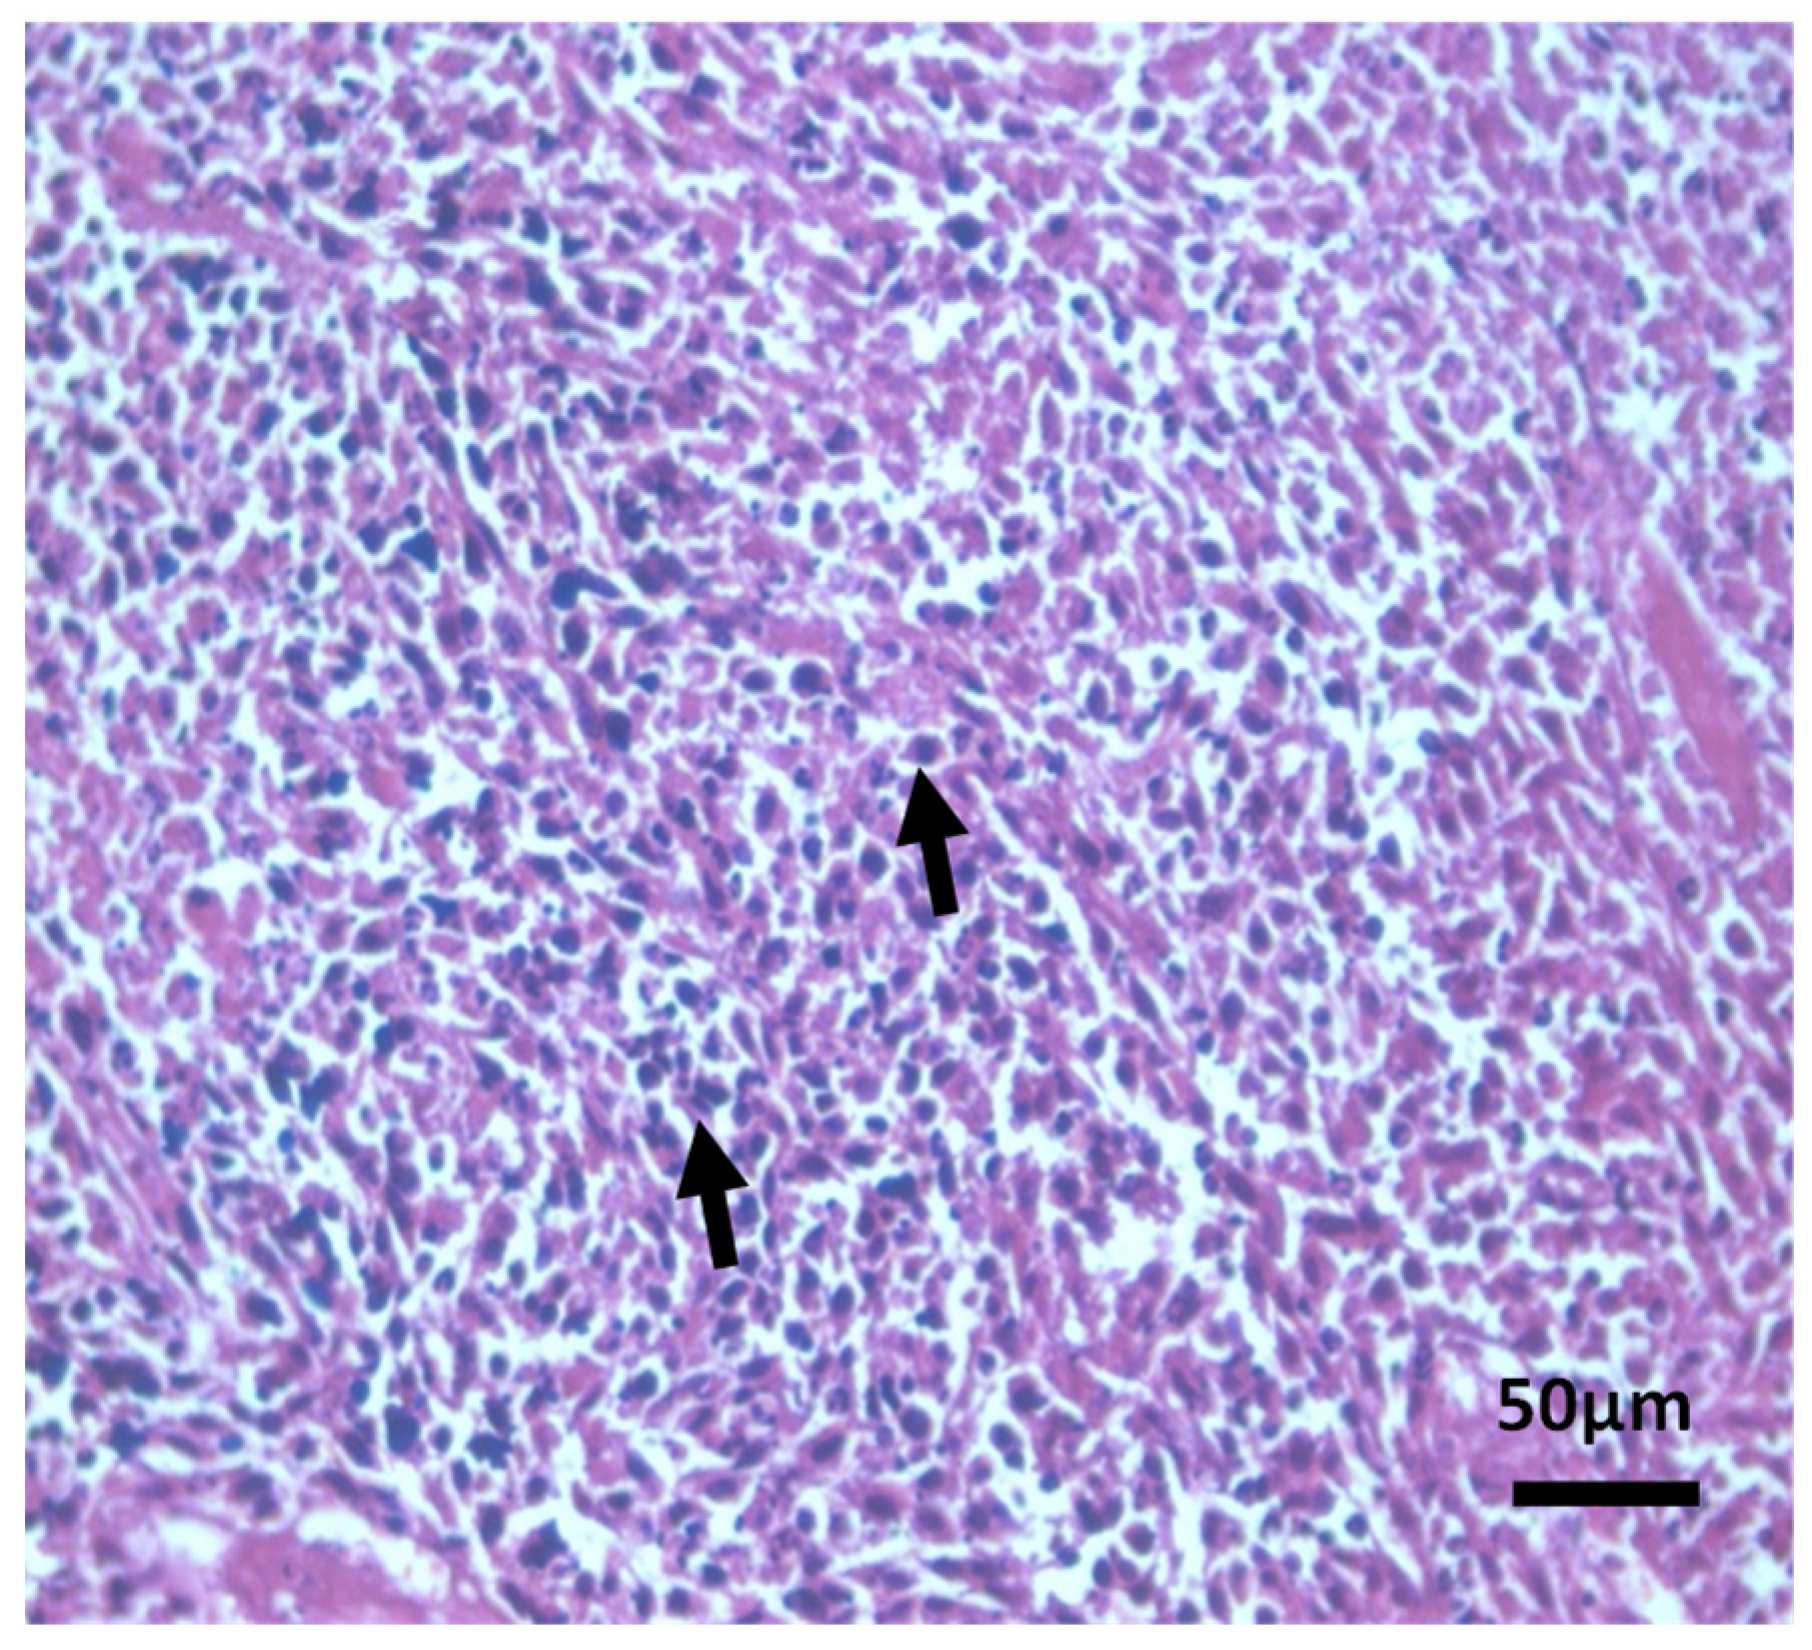

Histopathological Observations of Tissues